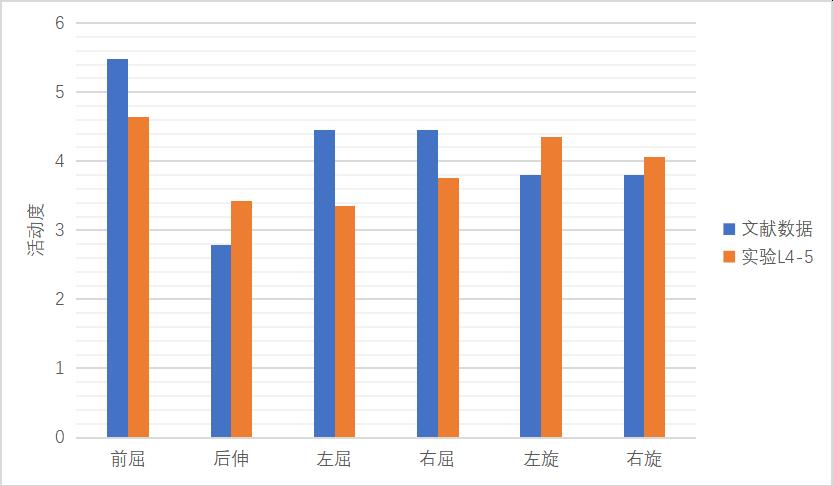

对L5椎体的下表面进行约束固定���,在 L3椎体上表面施加大小为500 N垂直向下的压力负荷��,充分反映健康人垂直站立时的腰椎承重情况��,同时在该表面节点及横突及棘突上表面施加 10 Nm的扭力负荷��,并加载前屈���、后伸���、左侧屈����、右侧屈����、轴向左旋转及轴向右旋转6种状态�����,其他约束条件不变��,可获得脊柱在6种功能状态下腰椎活动度的数值����,测量各节段的腰椎活动度�����,见图 14�����、图 15����。

图 15 L4-5模型有效性验证

1����、正常有限元模型(M0)L3-4节段在前屈���、后伸�����、左屈����、右屈����、左旋���、右旋的活动度为4.12°����、3.2°����、3.04°����、3.02°����、3.23°�����、3.38°��;L4-5节段在前屈�����、后伸���、左屈����、右屈��、左旋����、右旋的活动度为4.46°���、3.42°��、3.36°�����、3.76°��,4.35°���,4.26°��。与文献比较���,模型中各节段不同状态活动度数据均在正常范围之内���,证明该模型基本符合人体实验����,可用于有限元相关研究��。